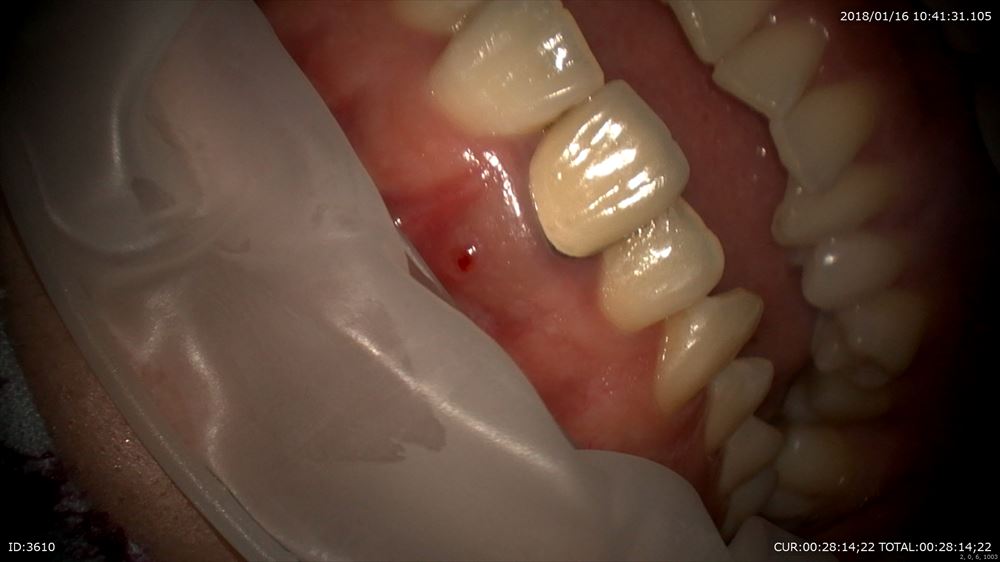

この方はまだ若いのに重度の虫歯を放っておいてこんなになってしまいました。

皆さん虫歯は絶対に放置しないでください。こんな状態になってしまいます。明らかに保存は難しそう。